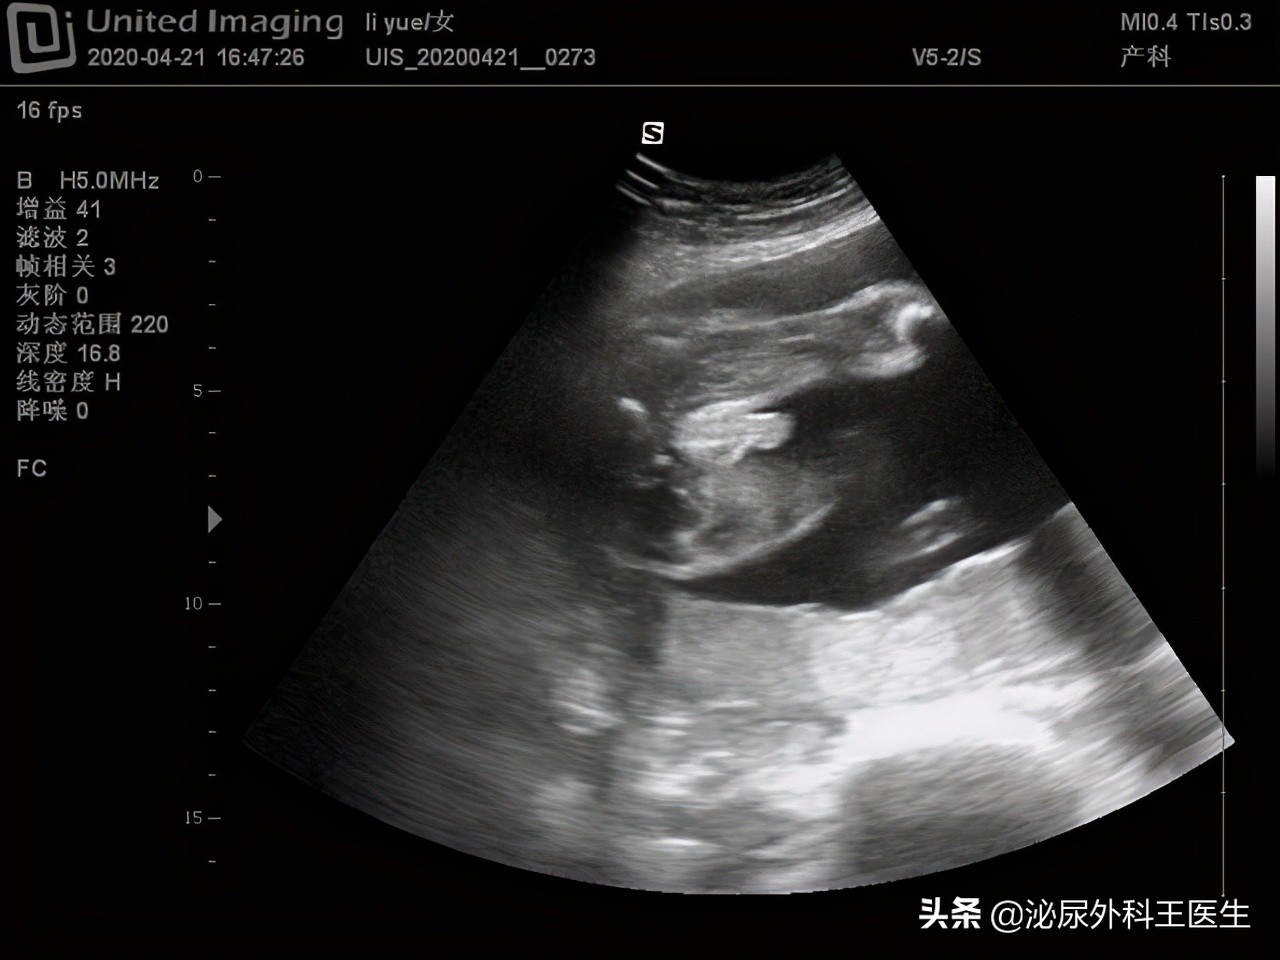

现代医学发展非常的迅速,早在1950年B超就投入到临床中使用, B超是B型超声的简称,B超是一些临床疾病的基础诊断方式。 B超的检查范围也非常的广泛,例如腹部超声,妇科超声,泌尿超声,心脏超声等。 “阴式”超声是B型超声的一种检查形态,阴式B超的探头较腹部超声的探头分辨率更高, 因此阴式超声比腹部彩超更清晰,诊断更明确, 主要用于妇科检查 。很多女性朋友虽然做过阴式超声的检查,但是对阴式超声还是并不太了解,而且有很多女性朋友出于传统观念,并不愿意做阴式B超检查。

阴式超声也可以称为腔内超声, 是将B超探头放入阴道进行超声检查的一种诊断方法 。传统的B超检查妇科,需要患者憋尿,而阴式B超则不需要, 免去了患者憋尿的痛苦 。阴式超声可以清楚的检查患者的盆腔脏器、子宫、附件、卵巢等。阴式B超相较于传统的B超 图像更清晰,结果更准确 。但是相较于传统的B超,阴式超声的价格也相对更贵一些。

阴式B超成像清晰 ,可以清楚的发现子宫、卵巢以及输卵管的异常情况,血运情况。而且还可以更早地 确认早期妊娠。阴式B超还可以检查宫颈糜烂的情况, 这是传统的B超检查做不到的。